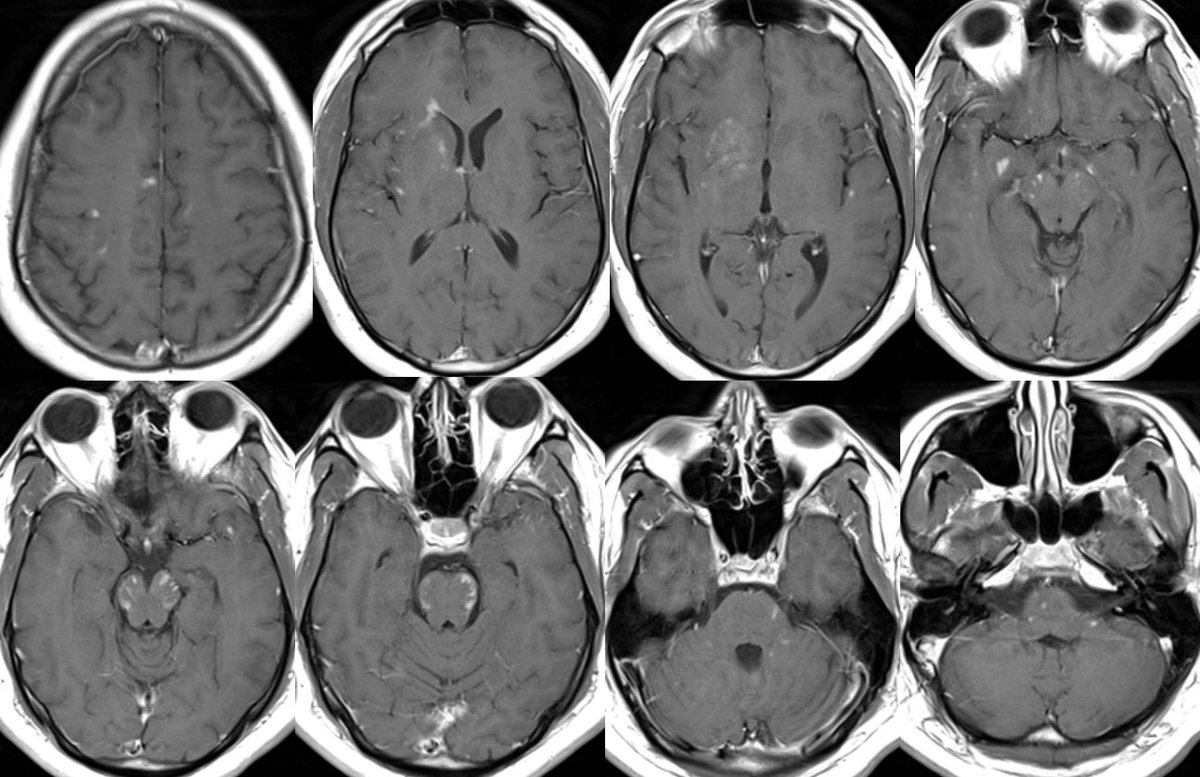

What is the most likely diagnosis in this 30 y/o M presenting w/ a few weeks of headaches, photophobia, vision loss, confusion, and ataxia?

Answer: MOG antibody-associated disease (MOG-AAD)

Path: MOG-AAD is an autoimmune inflammatory demyelinating disease targeting oligodendrocytes (NMO targets AQP4)

4️⃣Brain findings occur in <50% and may be ADEM or CLIPPERS-like with typical involvement of deep gray and posterior fossa